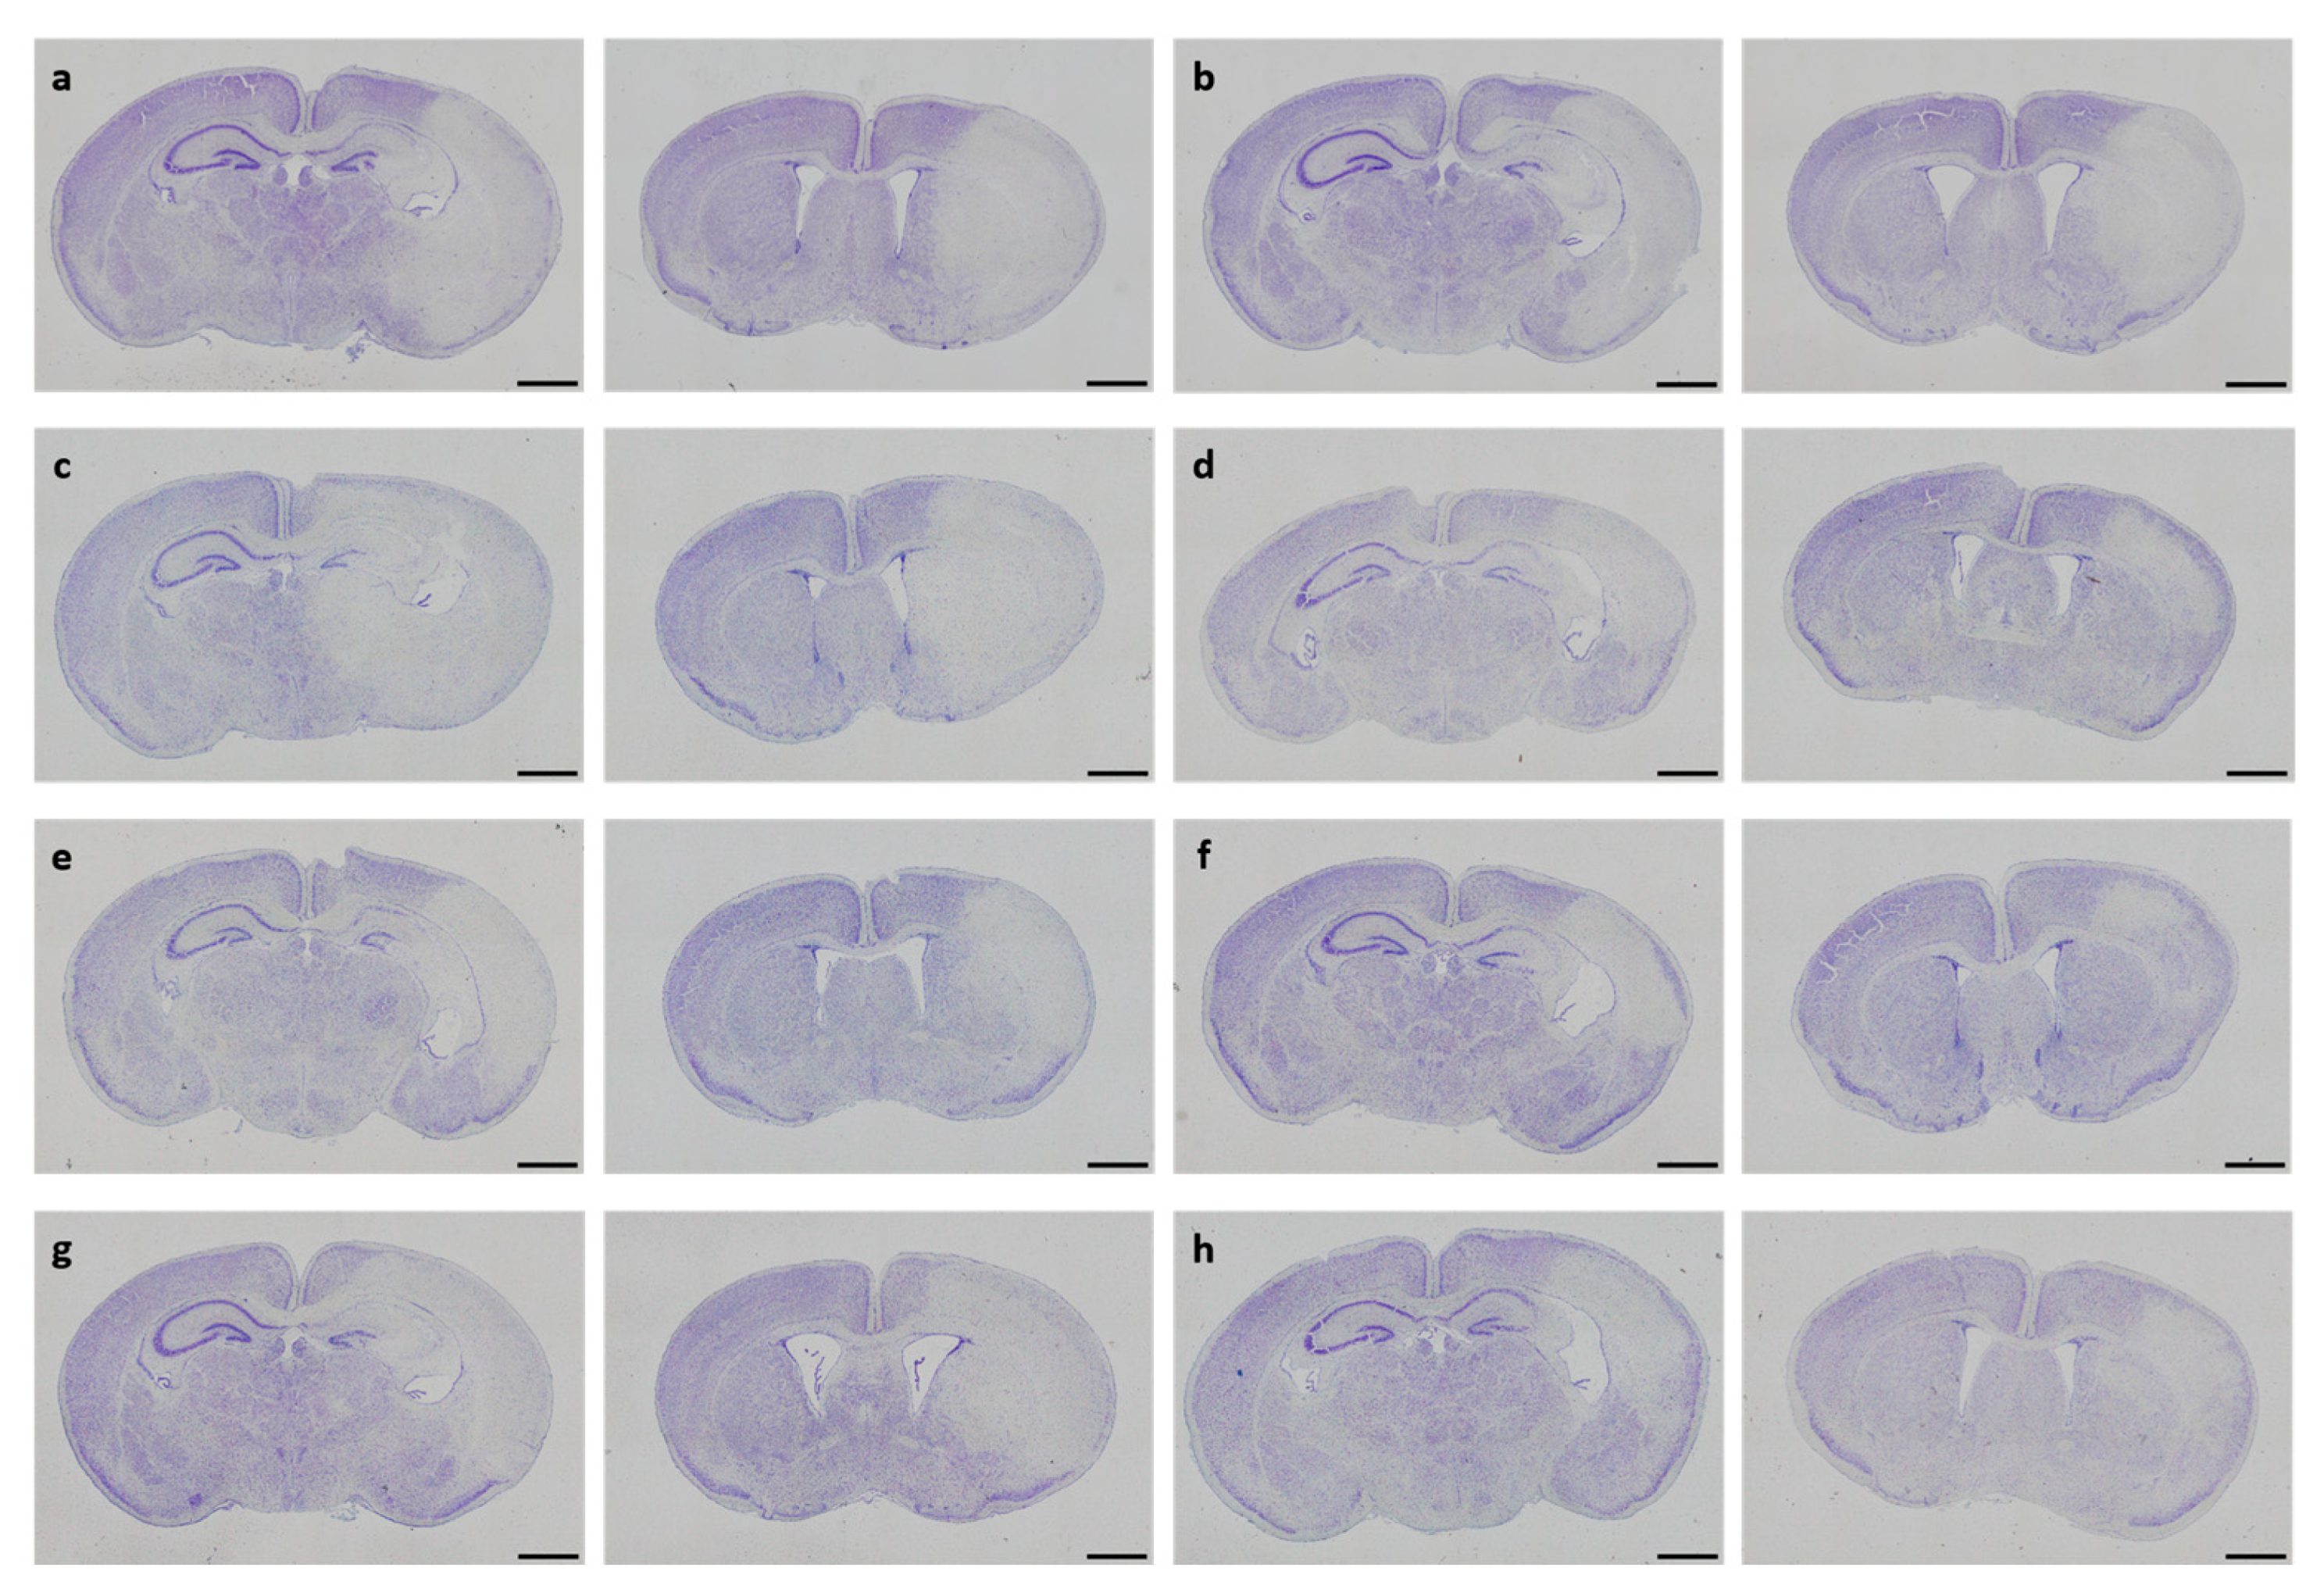

Figure 3.

Neuropathological injury assessment. Representative images of Cresyl Violet-stained coronal brain sections displaying hypoxic–ischemic injury in different treatment groups (a–h). Whole-brain visualization was performed using a 40-fold magnification (scale bars = 1000 µm). Two coronal section planes corresponding to coronal level 72 (bregma −1.755 mm, left) and coronal level 44 (bregma 1.045 mm, right) are displayed per brain. Treatment groups are as follows: (a) control 1× PBS, (b) solvent control 1× PBS + DMSO, (c) DHEA 0.1 µg/g bodyweight (bw), (d) DHEA 1 µg/g bw, (e) DHEA 10 µg/g bw, (f) DHEAS 0.1 µg/g bw, (g) DHEAS 1 µg/g bw, (h) DHEAS 10 µg/g bw.

In neonatal CD-1 mice subjected to hypoxia–ischemia and treated i.p. after insult, a blinded observer assessed neuropathological injury using an established scoring system. No overall statistical differences in neuropathological injury extent were detected in the subscores or total injury score (all p > 0.05). Details regarding total injury scores are provided in Table 1. Representative images of Cresyl Violet stainings for neuropathological injury assessment are shown in Figure 3. No sex-specific differences were observable (all p > 0.05).